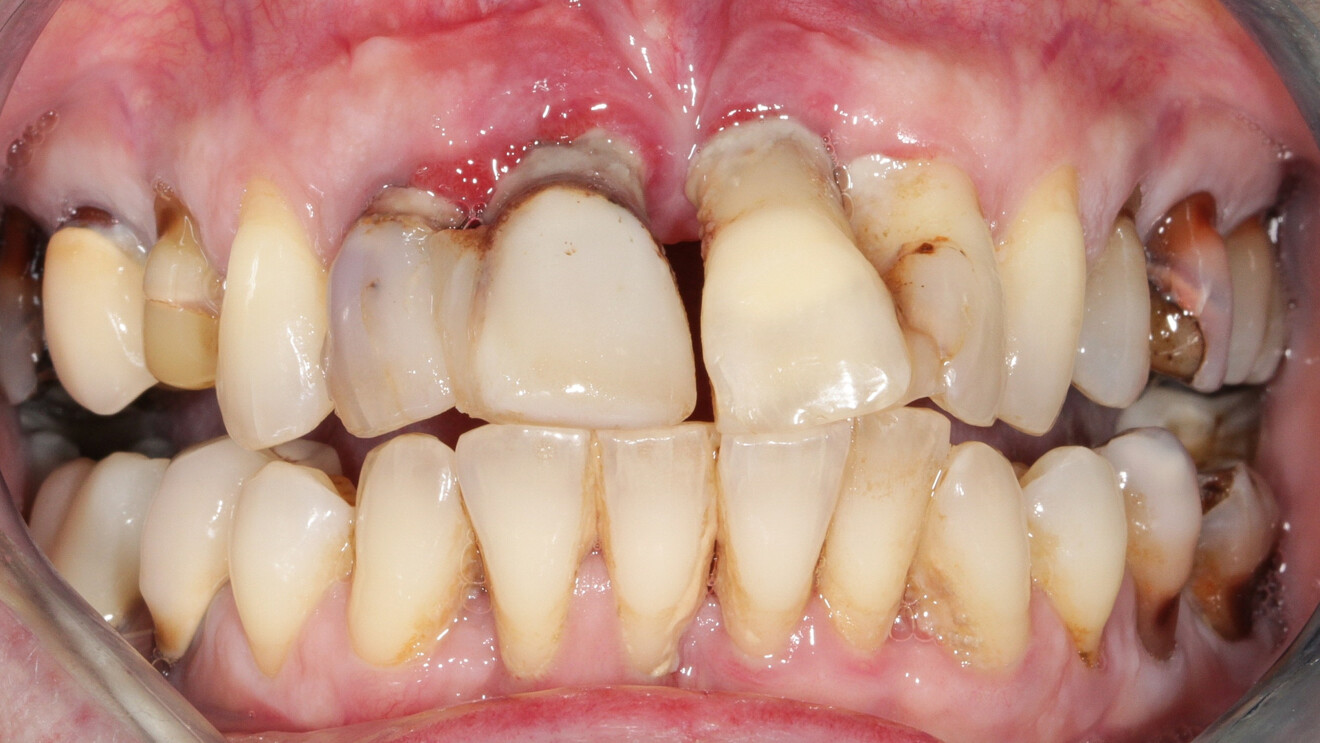

À l’examen, on observe une mobilité des quatre incisives maxillaires, une insuffisance osseuse verticale et horizontale, associées notamment au niveau de 11 et 21, la présence de plaque, de tartre et d’inflammation gingivale, surtout au niveau du bloc antérieur maxillaire. On note également la présence d’une dent de sagesse (dent 18) perdue (Figs. 24–26).